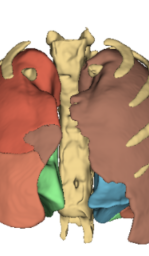

The AFP loss is computed using L1 loss in the feature space rather than in the pixel space. By comparing the feature representations of the synthesized and real images, we ensure that the model focuses on preserving high-level anatomical features rather than just pixel-wise intensity differences. The use of L1 loss in feature space is a well-established method in perceptual loss formulations, where it has been shown to improve the alignment of synthesized images with human perception of structure and detail (?). By leveraging feature representations from a segmentation network, we ensure that the AFP loss emphasizes medically relevant features, making it a more suitable choice for tasks like MR-to-CT translation, where preserving fine anatomical details is essential. Figure 1 illustrates an example of an MR to CT translation pipeline, where the AFP loss is applied to a U-Net network trained for airway segmentation.